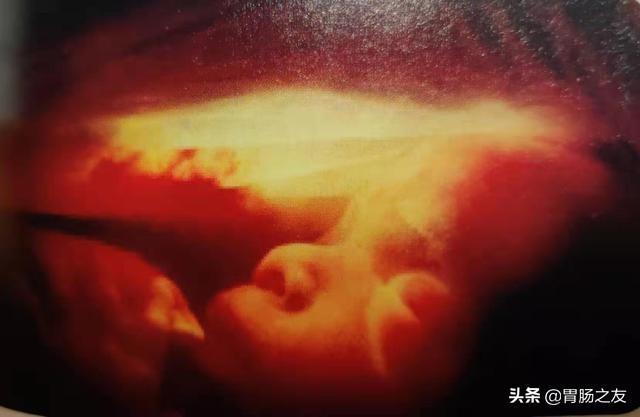

这张图显示的是一个5个月的胎儿面部发育特征,胎儿的眼睑粘合在一起直至孕晚期。